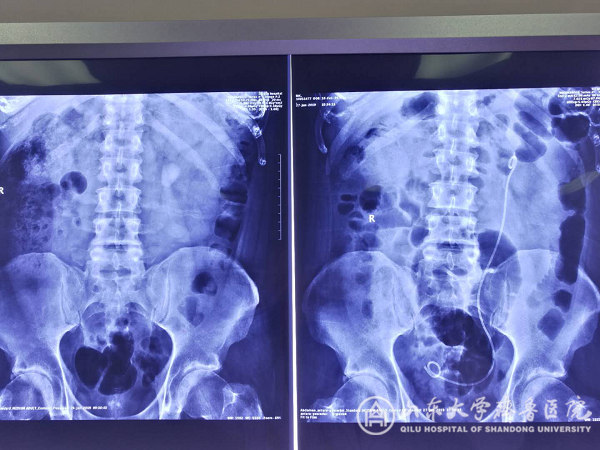

【本站讯】近日,在中国工作的英国教师RIK因患肾结石慕名来我院就诊,入院后泌尿外科二病区主任史本康主持全科讨论,由张东青教授团队为其行微通道无管化经皮肾镜碎石术,术中顺利将其3cm结石完全粉碎并排出,术后第1天即下床,第2天出院,住院时间仅5天。患者在围手术期未感觉到疼痛,对医护人员表示了由衷的感谢。

微通道无管化经皮肾镜碎石术相比于传统术式,其特点是患者痛苦小恢复快,手术创面仅为5mm刀口,但要求术者精准穿刺,拥有娴熟的通道扩张技巧及碎石清石技术。该技术已在我院开展近1年,受到广大患者一致认可。